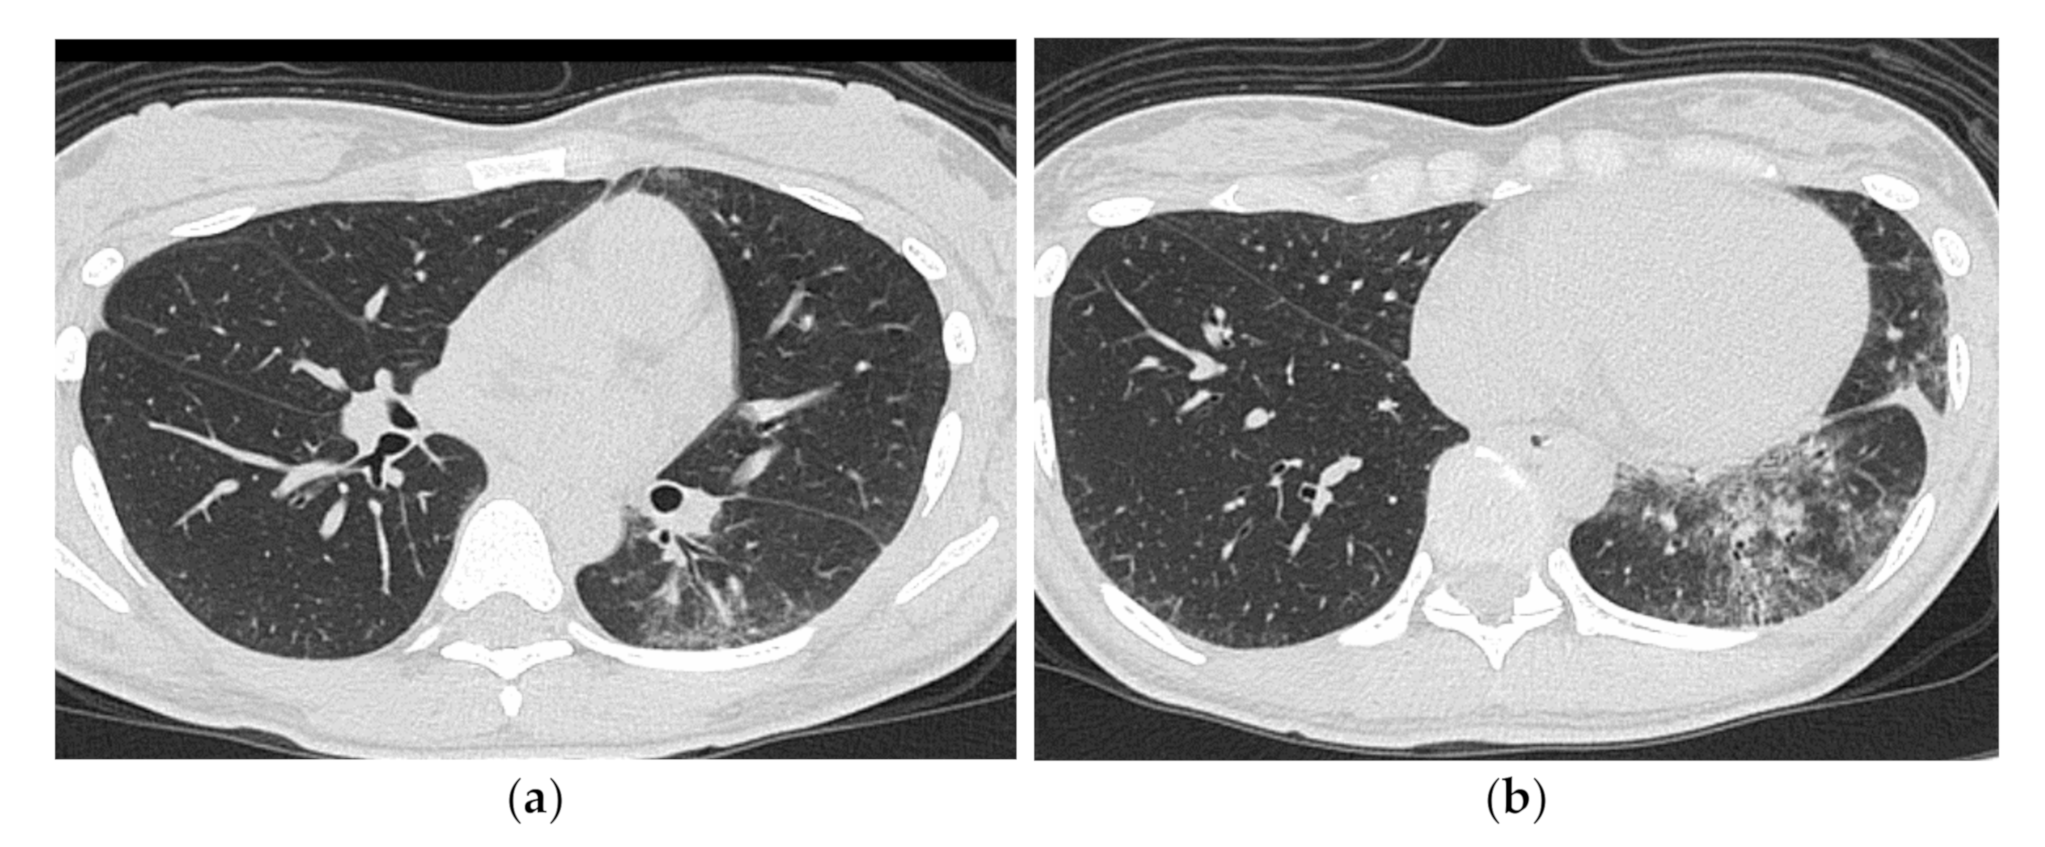

2.1. Subacute to Chronic Type

2.2. Acute Type